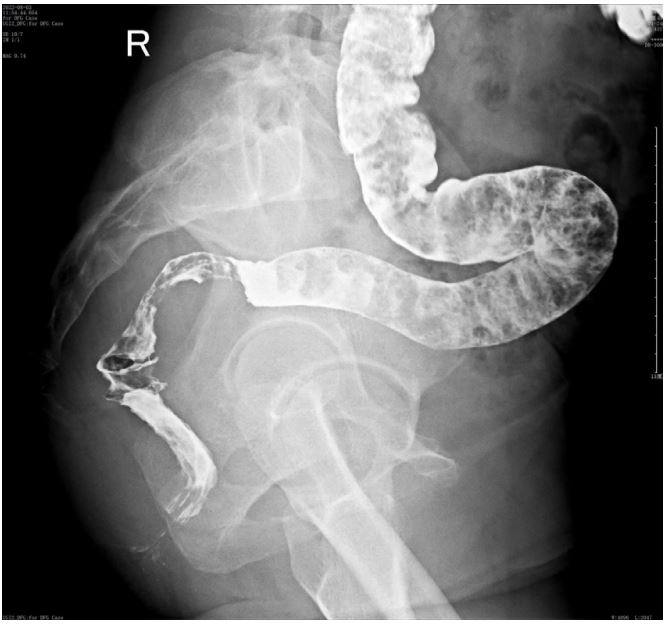

Colonic occupying lesion (whole abdomen enhanced CT is recommended). The intraoperative pictures are shown in Figure 2. Further CT examination suggested that: The intestinal wall at the junction of sigmoid colon and rectum was thickened with mass-like changes, the range was about 4.4 cm × 2.3 cm, the measured CT value was about 49HU, after enhancement, moderate enhancement was seen, the CT value was about 75HU, the plasma membrane surface of the intestinal canal corresponding to the lesion was still smooth; the distribution and morphology of the remaining abdominal intestinal canal did not show obvious abnormal changes, the mesenteric fat gap was still clear, and no obvious enlarged lymph nodes were seen. No obvious enlarged lymph nodes were seen. The bladder was full and no significant abnormal density foci were seen in the bladder. A small cystic hypodense foci, about 2.4 cm × 1.7 cm in size, could be seen in the right adnexal area, and no significant abnormal enhancement was seen after enhancement. The size and shape of the uterus were acceptable, and no significant abnormal enhancement was seen after enhancement. The biopsy report after colonoscopy suggested tubular adenoma (rectum) with mild heterogeneous hyperplasia of the glandular epithelium (low-grade intraepithelial neoplasia). The patient was referred to a general hospital for gastrointestinal surgery, where colon cancer was highly considered and a biopsy was performed, which showed tubular adenoma (rectum) with low-grade intraepithelial neoplasia. The patient refused further treatment and returned to the hospital 2 months later with no significant change in the symptoms of anal distention. After MTD discussion, colonoscopy was performed again with the patient’s informed consent, and the endoscopist was changed. The lesion was partially excised from the colon with adequate information, and endometriosis was considered in the intraoperative frozen section, and the excised tissue was shown in Figure 3. Immunohistochemical results: CK (AE1/AE3) (+), CK20 (-), CDX-2 (-),CD10 (+), ER (3+), PR (2+), WT-1 (+), p53 (~5%+), Ki67 (~10%+). All pathological images are shown in Figure 4. See Figures 9 and 10 for details. postoperative symptomatic treatment and recovery was good. Postoperative follow-up until the writing of this manuscript the patient was generally well with no significant discomfort.

Figure 2: First colonoscopy image.